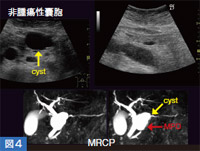

通常,2Dで腫瘍や嚢胞の体積計算を行う場合は,縦,横,厚みの3方向を計測して割り出しているが,計測位置がずれると数値が大きく変化してしまうことがある。一方,3Dでは,プローブのスイープ角の中に嚢胞がすべて納まるように設定すると,5秒以内で3Dの断面像として表示される。嚢胞のみをボリュームレンダリング(VR)表示することも可能であり(図1),エコーレベルのコントラストが十分に得られる症例では,例えばがんの化学療法や放射線治療後の経過観察などにおいて,体積の変化が視覚的に判断できるようになる。また,VR表示された嚢胞は,回転させてさまざまな方向から観察可能であり,嚢胞を取り出して内腔面の凹凸を見ることもできる。

図1